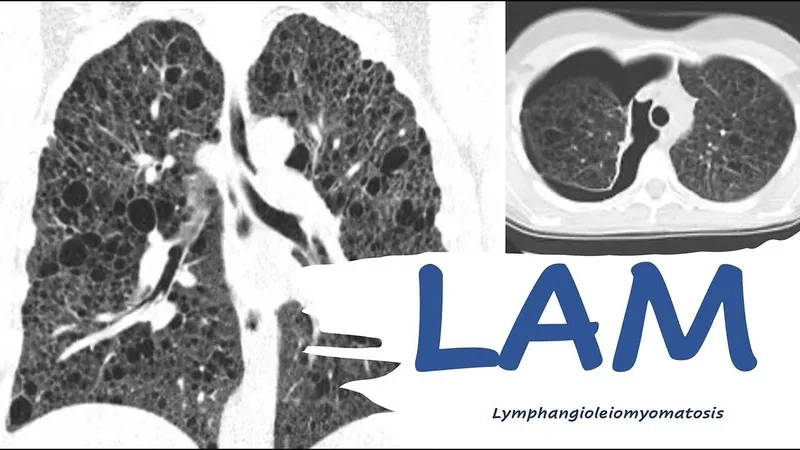

Lymphangioleiomyomatosis (LAM) - A rare lung disease in women

Medical illustration of LAM disease awareness